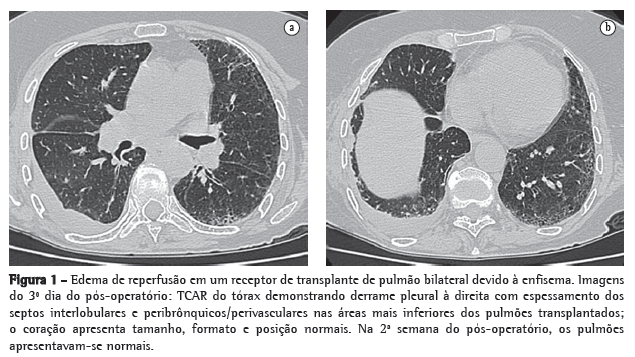

Apesar de a radiografia de tórax ser a forma mais comum de investigação radiológica, a TC pode fornecer informações adicionais valiosas (Figura 1). No pico de gravidade, o edema de reperfusão aparece nas zonas pulmonares superiores, médias e inferiores, como a doença intersticial reticular em 19%, 33% e 34% dos casos, respectivamente, ou como a doença dos espaços aéreos em 31%, 61% e 57% dos casos, respectivamente.(7) O edema de reperfusão é relatado como assimétrico em quase 20% dos pacientes submetidos ao transplante pulmonar bilateral.(7) As características na TC são inespecíficas e podem incluir opacidades alveolares peri-hilares, espessamento peribrônquico/perivascular, derrame pleural (Figura 1) e opacidades reticulares intersticiais/espaços aéreos localizados predominantemente no lobos médios e inferiores.(7)